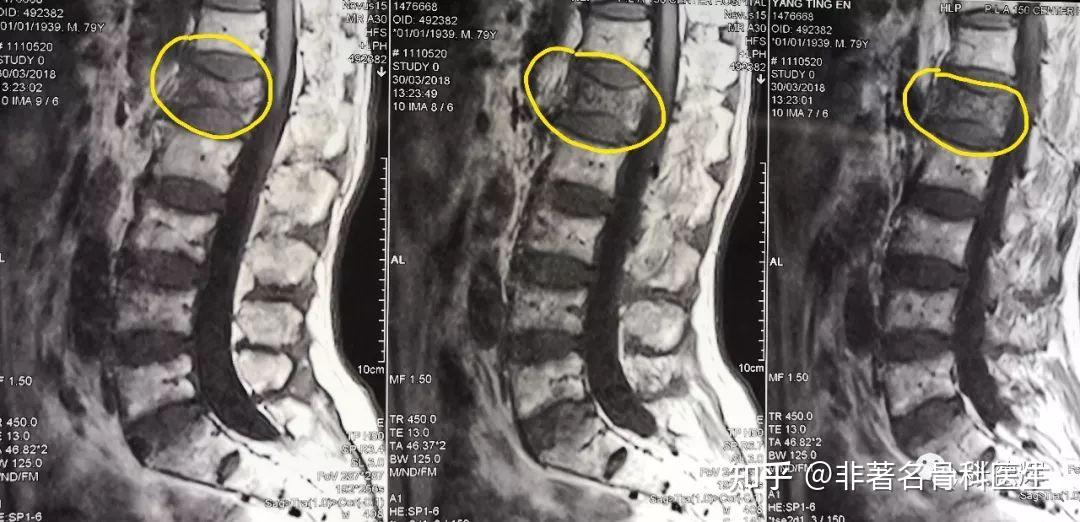

高龄腰椎骨质疏松性骨折pvp(骨水泥注射成型术)

腰椎核磁共振影像(mri)显示l5节段t1相(a)和t2相(b)相似的低中

术前腰椎mri t1显示:腰2-3椎管内占位病灶,呈等信号,边界清晰,同马尾